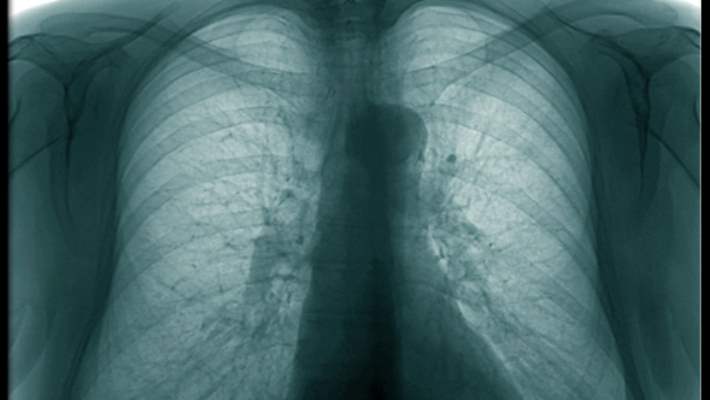

Kronik Bronşit Nasıl Teşhis Edilir?

Doktorunuz tıbbi geçmişinizi değerlendirdikten ve fiziksel muayene yaptıktan sonra pulmoner fonksiyon testi önerebilir. Pulmoner fonksiyon testleri spirometri gibi akciğerlerinizin ne kadar iyi çalıştığını ölçer. Göğüs röntgeni de çekilebilir.